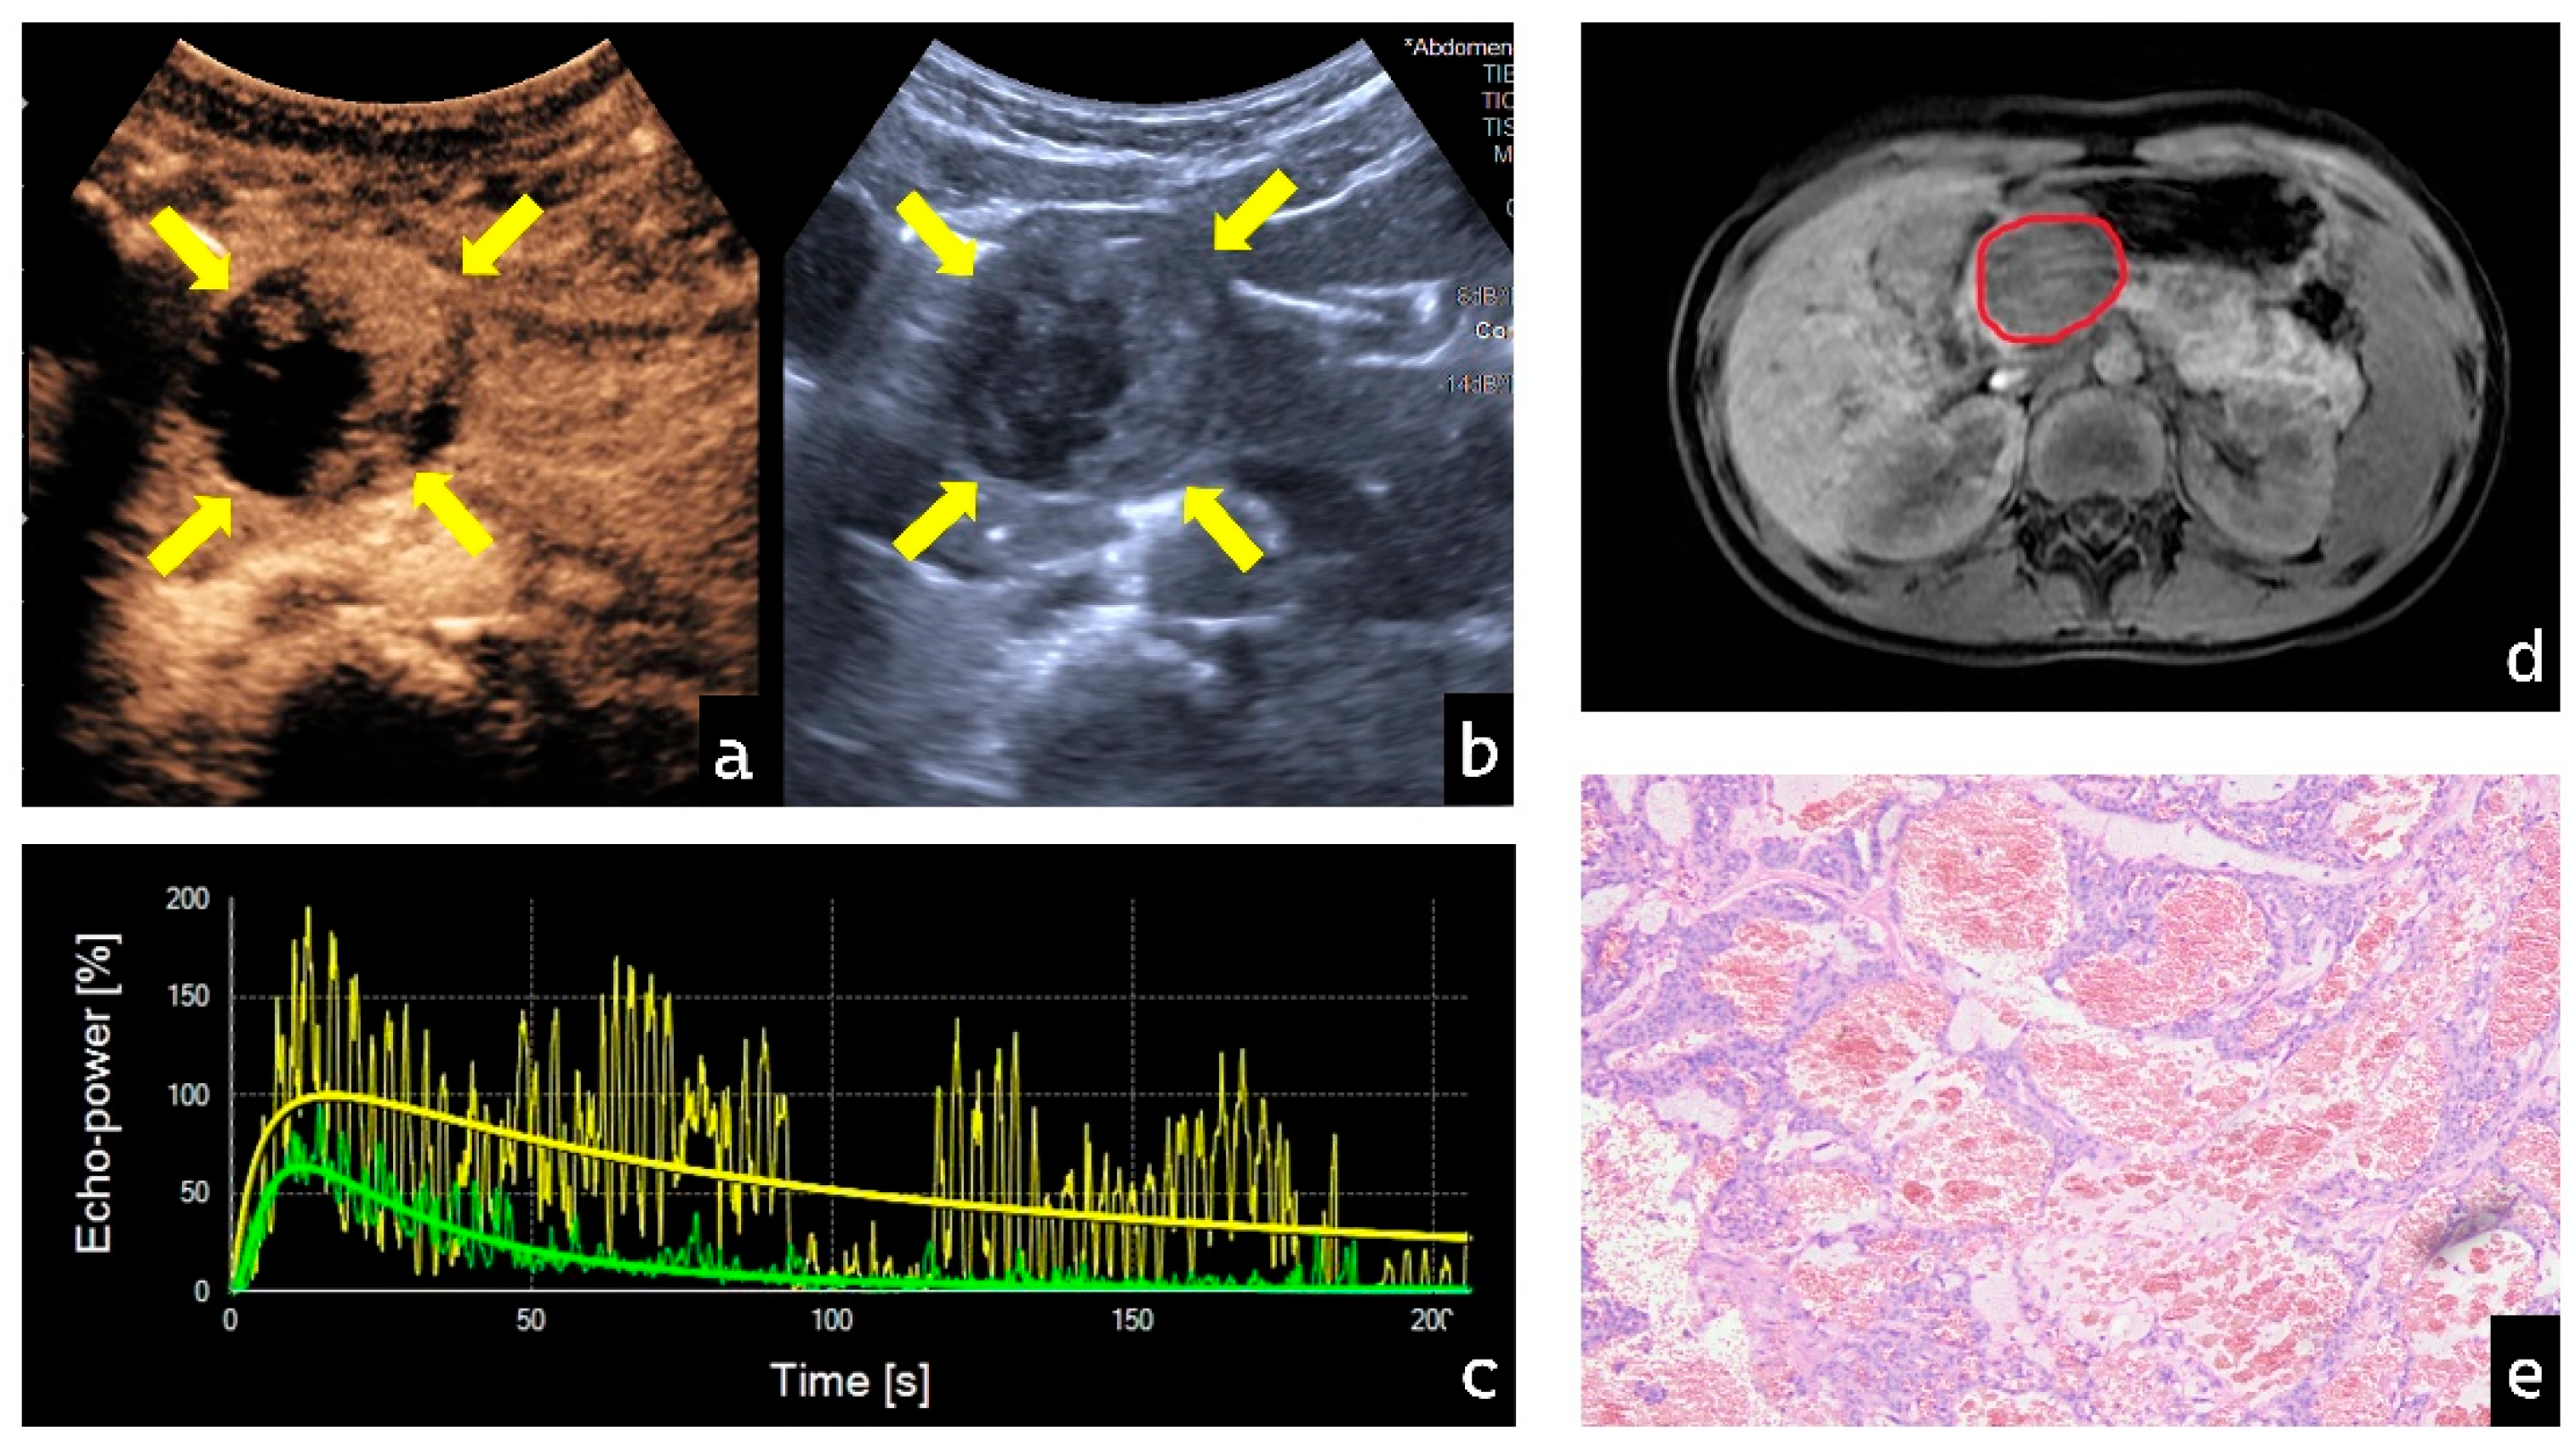

3.4. Visualization of Representative Cases